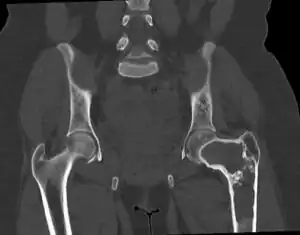

Fibrous dysplasia of the top of thigh bone at the hip | |

On x-ray, fibrous dysplasia appears as bubbly lytic lesions, or a ground glass appearance. Computerized tomography (CT) or magnetic resonance imaging (MRI) scans may be used to determine how extensively bones are affected. CT can better demonstrate the typical "ground glass" appearance, which is a highly specific radiological finding, while MRI can show cystic areas with fluid contents.[18] A bone scan uses radioactive tracers, which are injected into the bloodstream. The damaged parts of bones take up more of the tracer, which show up more brightly on the scan. A biopsy, which uses a hollow needle to remove a small piece of the affected bone for laboratory analysis, can diagnose fibrous dysplasia definitely.